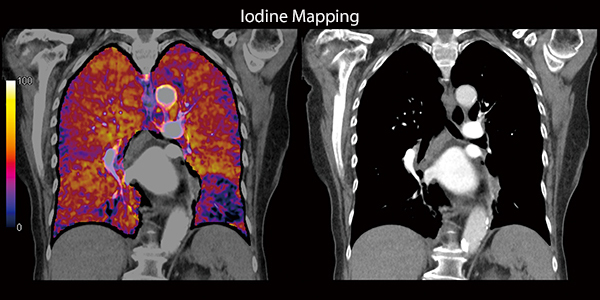

Передовые клинические решения Canon Medical гарантируют превосходную визуализацию сосудистой сети в исследованиях CTA, в то время как Iodine Mapping обеспечивает дополнительный уровень детализации в рамках

Йодное картирование

Четко определенное распределение йода с цветными картами кровотока